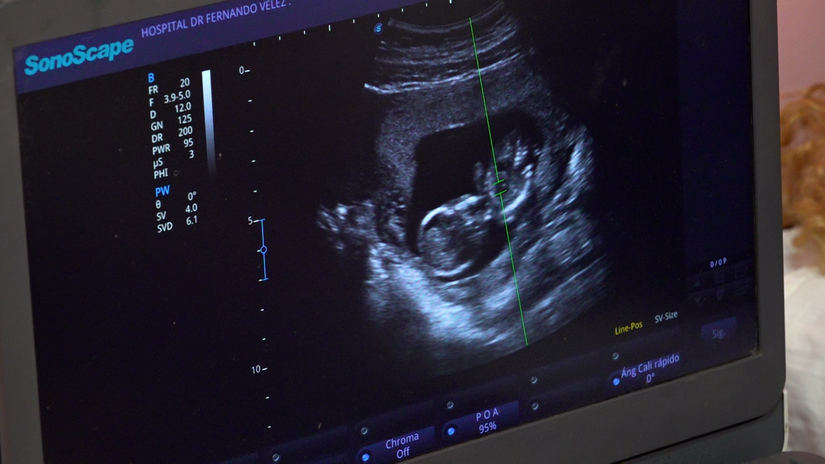

La doctora Judith García, directora del centro, comentó que a las mujeres se les realizan ultrasonidos para evaluar la edad gestacional y el riesgo de presentar alguna anomalía congénita, preeclampsia o embarazo pretérmino.

“Estamos realizando estudios a mujeres entre las 11 y 13 semanas de embarazo, con una evaluación completa de su gestación, con un ultrasonido específico de tamizaje, en el cual se evalúan entre 100 y 150 embarazadas, provenientes de todo el departamento de Managua y del Silais-Managua”.